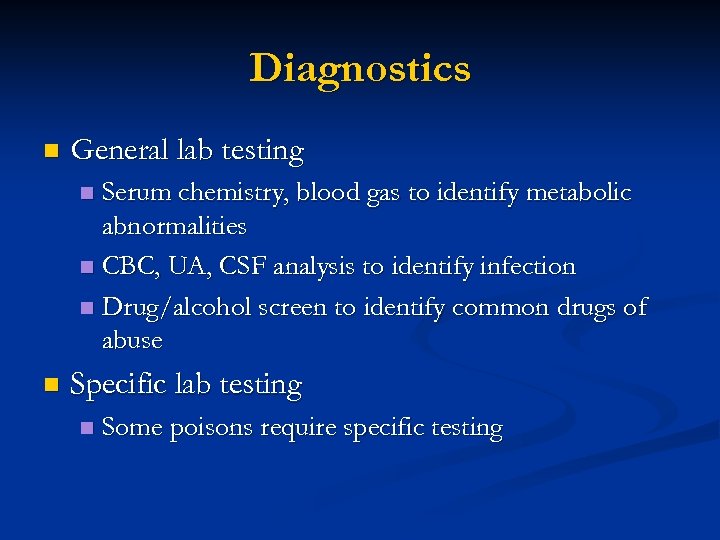

Diagnostics n General lab testing Serum chemistry, blood gas to identify metabolic abnormalities n CBC, UA, CSF analysis to identify infection n Drug/alcohol screen to identify common drugs of abuse n n Specific lab testing n Some poisons require specific testing

Diagnostics n General lab testing Serum chemistry, blood gas to identify metabolic abnormalities n CBC, UA, CSF analysis to identify infection n Drug/alcohol screen to identify common drugs of abuse n n Specific lab testing n Some poisons require specific testing